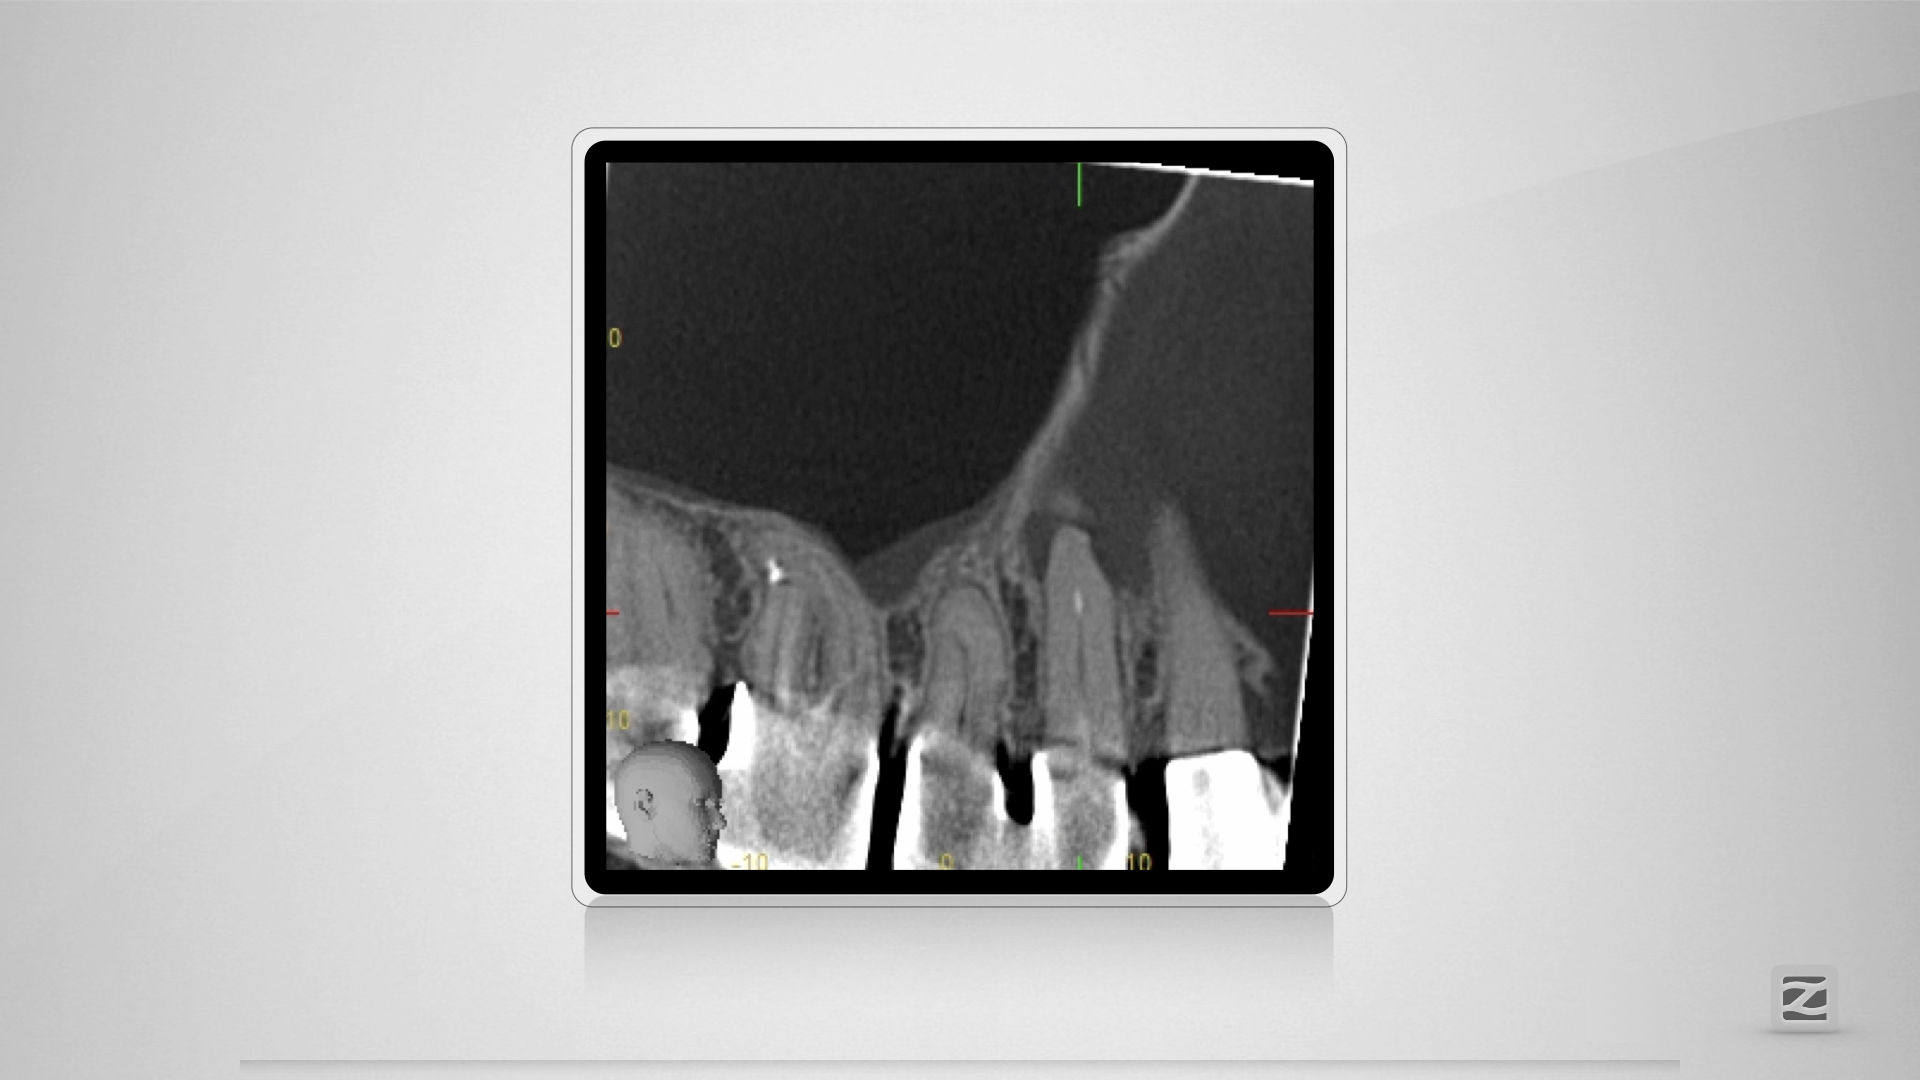

14D.006

Dummheit gehört bestraft.